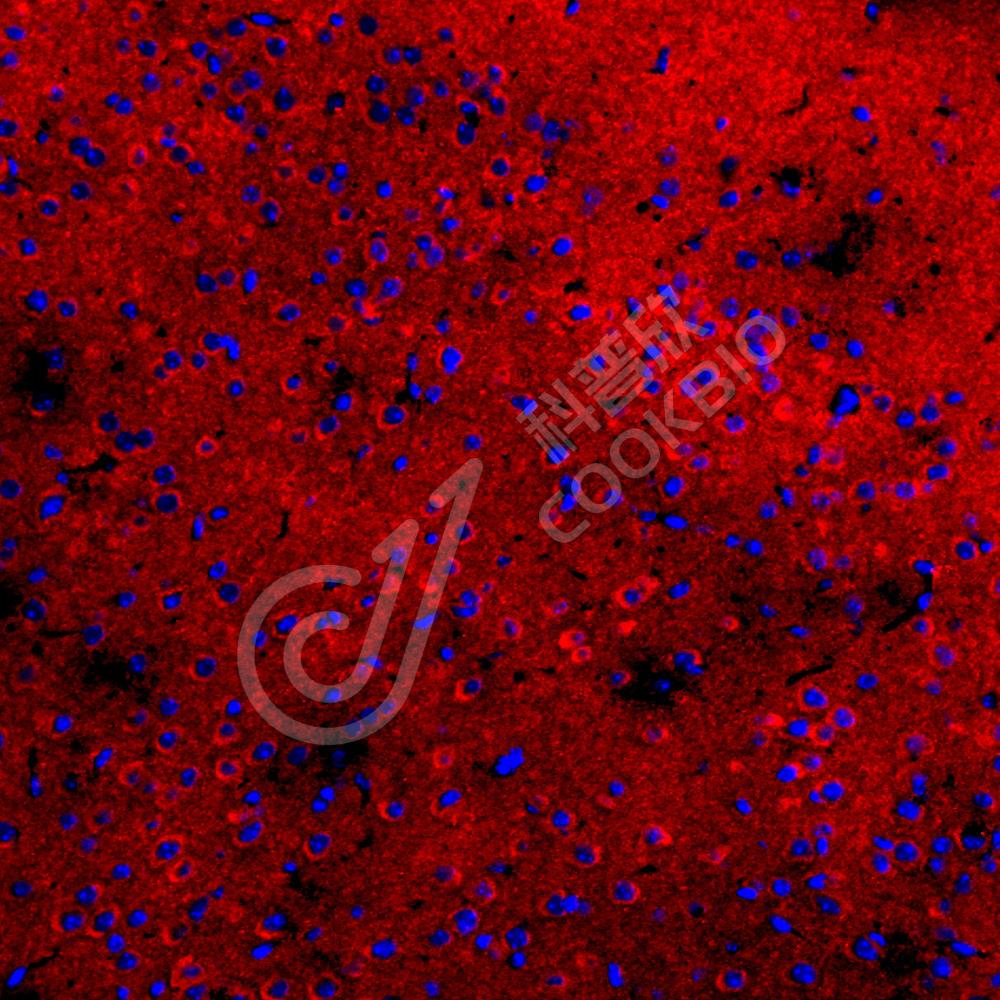

IF检测Tau蛋白(货号 K1334827)(红色).

样品: 大鼠脑, 4%多聚甲醛 (货号KSG1101) 固定12-24小时.

抗原修复: Tris-EDTA抗原修复液(pH 9.0) (KSG1203), 98℃, 20分钟.

封闭: 3% BSA(货号KSGC305010)的PBS溶液, 室温孵育30分钟.

—抗: 1: 1500稀释, 4℃ 孵育过夜.

二抗: Cy3标记山羊抗兔IgG (H+L) (货号KB63909), 1: 300稀释, 室温孵育1小时.